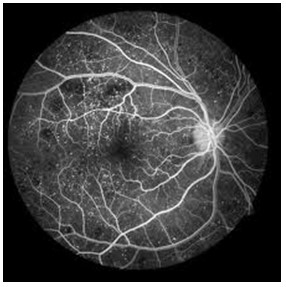

b. Fundus Fluorescein Angiography

This diagnostic procedure utilizes a specialized fundus camera or scanning laser ophthalmoscope to capture rapid-sequence photographs of the retina following an intravenous injection of fluorescein sodium. Photographic or video images taken as the dye courses through the eye can demonstrate abnormalities within the neurosensory retina, pigment epithelium, sclera, choroid, and optic nerve, providing clinically useful information for nearly the entire spectrum of posterior segment disorders.

DR 1 DR 2